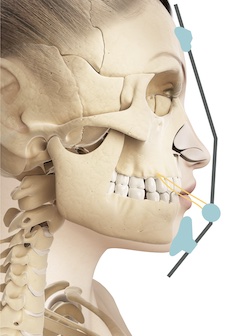

Análise de Crescimento Nesse curso vamos conversar sobre avaliação do pico de crescimento puberal. E por que odontopediatras ou ortodontistas precisam identificar o pico de